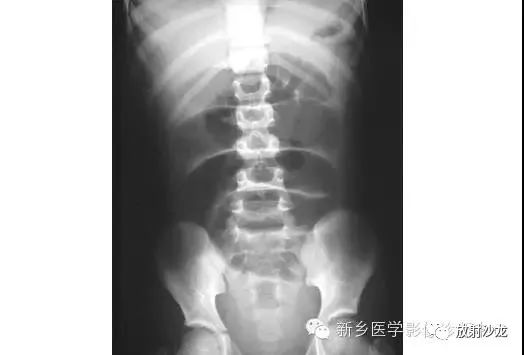

腹部脏器有实质器官和空腔脏器之分,其正常腹平片表现不同。

● 腹平片上实质器官的正常表现:

实质器官:肝、胰、脾和肾等是中等密度,但借助于器官周围或邻近的脂肪组织和相邻充气肠胃的对比,于腹平片上,可显示器官的轮廓、大小、形状及位置。

正位片在部分病人可显示肝下缘,肝下缘与肝外缘相交形成肝角,一般呈锐角。

脾上极与左膈影融合,下极较圆钝。而肾沿腰大肌上部排列。

胰腺于平片上不易显示。子宫偶尔显影,位于膀胱上缘上方呈扁圆形软组织影。

● 空腔脏器在腹平片上的主要表现:

空腔器官:膀胱的脏壁为中、胆囊和肠胃道等密度,依腔内容物不同而x线表现不同。

胃、十二指肠球部及结肠内可含气体,于腹平片上可显示其内腔。小肠除婴幼儿可有积气外,一般充满食糜及消化液,与肠壁同属中等密度,因缺乏对比而不能显示。

如胃内有较多固态食物,结肠或直肠内有较多粪便,由于它们周围有气体衬托,故可显出软组织密度斑片或团块影。

结肠分布于腹部四周。膀胱和胆囊周围有较多脂肪,也可显示部分边缘。